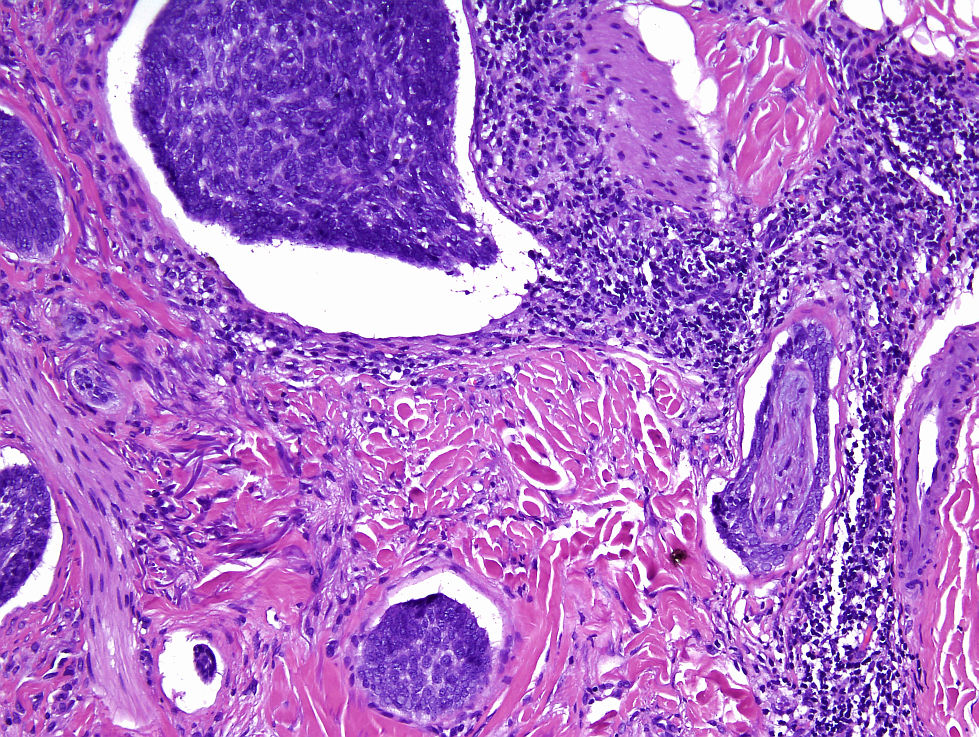

Cas dermatopaotologia. Dona de 36 anys amb pàpules pruriginoses vulvars

Juny 2013